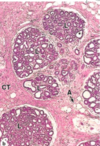

באיזה שלב הביצית בתמונה?

A מה מסומן ב?

GC מה מסומן ב?

TI מה מסומן ב?

TE מה מסומן ב?

secondary follicle

antrum- מעיד על השלב (חלל נוזלי)

granulosa cells

theca internal (קפילרות, מפרישה הורמונים)

theca external (פיברובלסטים ושריר חלק)

באיזה שלב הביצים בתמונה?

מה מסומן בחץ מספר 1?